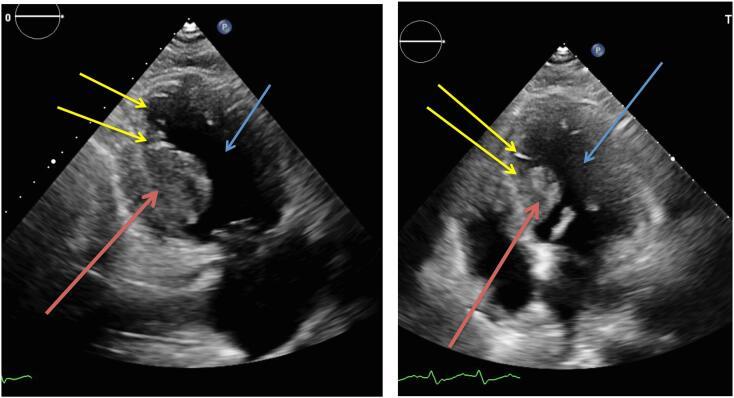

A seventy-one year old male was presented at our Emergency Department with complaints/ signs of dyspnoea, low blood pressure, tachycardia/atrial fibrillation, diarrhoea and general malaise. Trans Thoracic Echocardiography (TTE) was performed which showed a mass in the left ventricle suspect of malignant origin. After five days of hospital admission the patient died due to refractory shock. Autopsy reports showed extensive cardiac, spinal, peritoneal, peripheral fat and muscle tissue metastasis, due to the sarcomatoid urothelial cell carcinoma.

一名71岁男性因呼吸困难、低血压、心动过速/心房颤动、腹泻和全身不适等症状/体征就诊于我院急诊科。经胸超声心动图(TTE)检查显示左心室有一个疑似恶性起源的肿块。入院五天后,患者因顽固性休克死亡。尸检报告显示,由于肉瘤样尿路上皮细胞癌,心脏、脊柱、腹膜、外周脂肪和肌肉组织出现广泛转移。